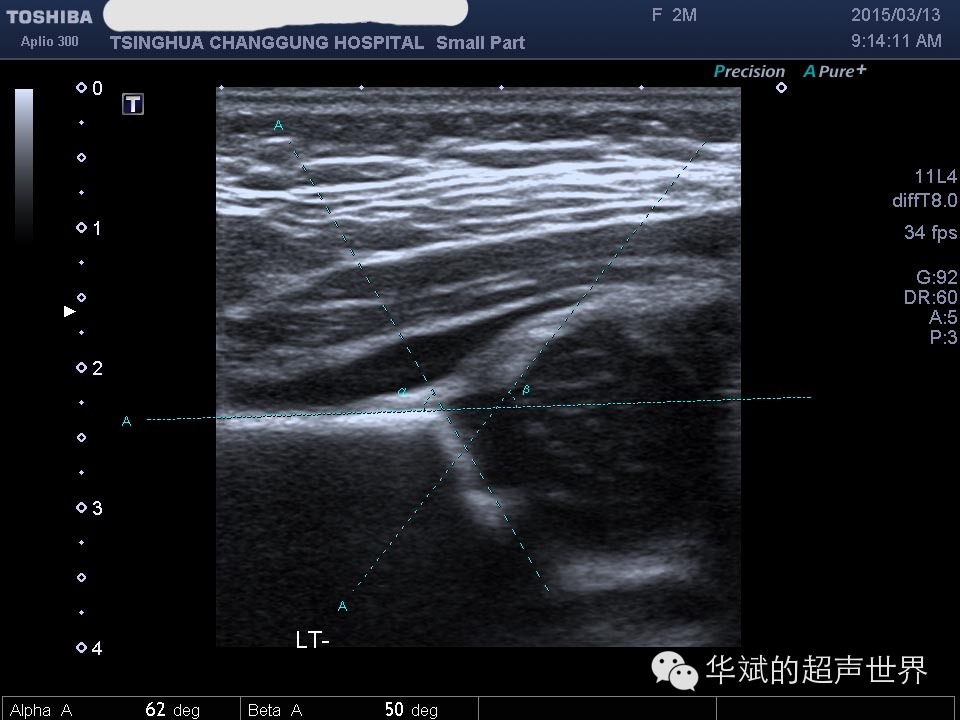

对于成熟髋关节的测量没有异议,应该如下图所示

图3 成熟髋关节的测量。

我们首先了解一下α角和β角的含义。Graf在设计这两个角度时候是把α角和β角分别用以代表骨性髋臼顶和软骨性髋臼顶。α角越大骨性髋臼顶的范围越大,β角越大软骨性髋臼顶的范围约大。

附:α 值可以分作3大部分:

①≥60°,I 型髋关节(成熟髋关节);

②43°~59°,II 型髋关节(α = 50°~59°:生理性不成熟-发育不良,α =43°~49°:髋臼发育存在缺陷-严重发育不良);

③<43°,偏心型关节-脱位。意味着髋臼很平,股骨头不能通过髋臼软骨顶保持在原发髋臼中,而从髋臼中脱出。